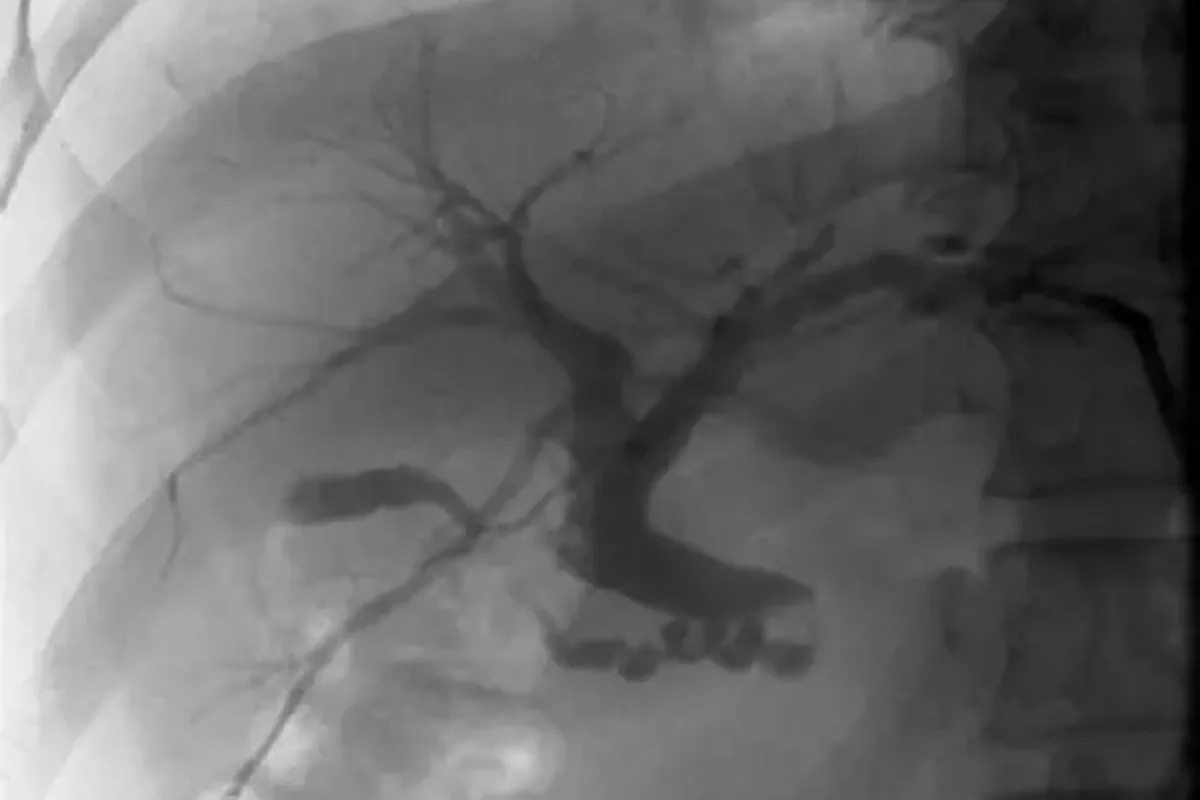

Peripheral Angioplasty procedure at Sarda Vascular Centre Dehradun

Interventional Radiology (IR) uses real-time imaging such as X-ray, ultrasound, CT, or MRI to guide tiny instruments through the body for treatment — without large surgical incisions.